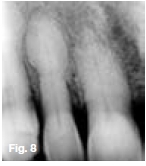

Figures 1, 2, & 3 show a mixed radiolucent/opaque lesion affecting the maxilla, crossing the midline in an edentulous patient, causing flattening of the palate. A lateral skull radiograph of another patient (Fig. 4) shows osteoporosis imperfecta in the posterior and anterior parts of the skull (green arrows) along with thickening of the calvarium and cranial vault which are cardinal radiological signs of the condition. Figures 5 & 6 illustrate "cotton wool" radio-opacities in the skull and the base of the skull shows dense sclerosis. All the images mentioned so far are typical features of Paget's disease. Sir James Paget, surgeon and pathologist who is best remembered for naming Paget's disease. The disease is idiopathic and can be divided into three stages: initial bone resorptive phase, vascular phase with osteoblastic repair, and approximal/ sclerosing phase. The jaws are involved in approximately one in Ave cases, with the maxilla being affected about twice as frequently as the mandible. During the initial phase of bone resorption, the affected bones may be deformed or painful, particularly the weight-bearing structures such as the long bones of the legs (Fig. 7A & B). Later the affected bones expand, commonly in the maxilla, mandible or cranium. At this stage, the dental patient who wears full dentures may complain that the fit of the dentures is becoming progressively poorer. When the maxilla is affected, the alveolar ridge widens and the palatal vault can flatten (Fig. 2). When teeth are present, they may become increasingly spaced, with extensive jaw enlargement. Neurologic complaints can result from increased deposition of bone in the areas of the foramina of the skull causing headaches, auditory disorders progressing to deafness, visual disorders progressing to blindness, facial paresis, and vertigo. The bones are relatively brittle; hence, fractures are likely. Generalised radiolucency/osteoporosis intermediate stage with mixed radiolucency/radiopacity, "driven snow" coarse trabeculation, "cotton wool" radio-opacities in the final stage (Figs. 5 & 6). Hypercementosis, loss of lamina dura, obliteration of the periodontal ligament spaces (Fig. 8) and external root resorption (Fig. 9) may also be present. The upper hand wrist radiograph (Fig.10) of another patient shows the disease affecting the phalanx of the third digit.